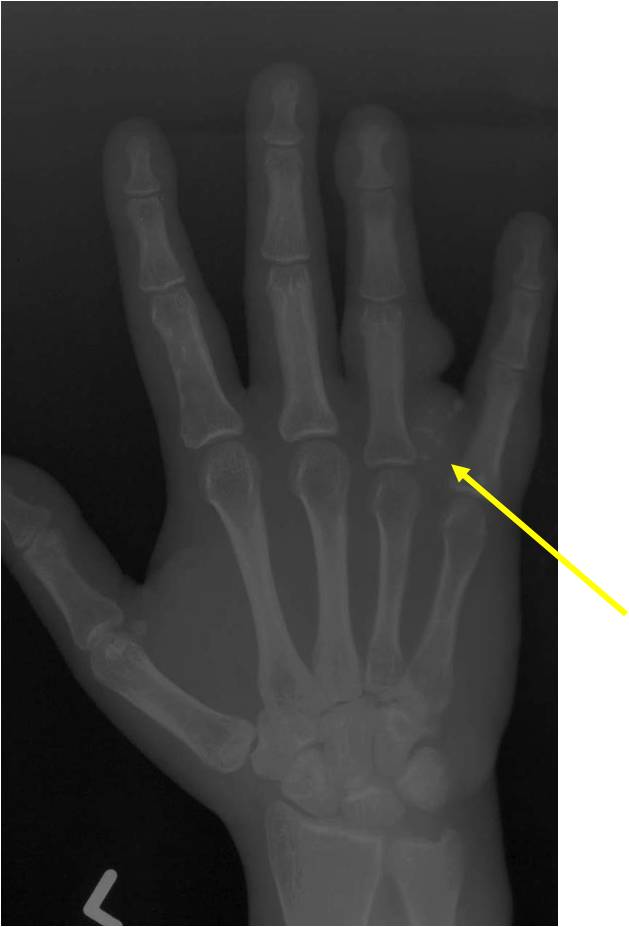

Geographic Lesion Bony Expansion Minimal Calcification Some Enchondromas do not calcify

Geographic lesion, Stippled calcifications in lesion, Phalanx is expanded, Significant endosteal scalloping, No cortical destruction, No soft tissue extension, Cortex Scalloped and Expanded